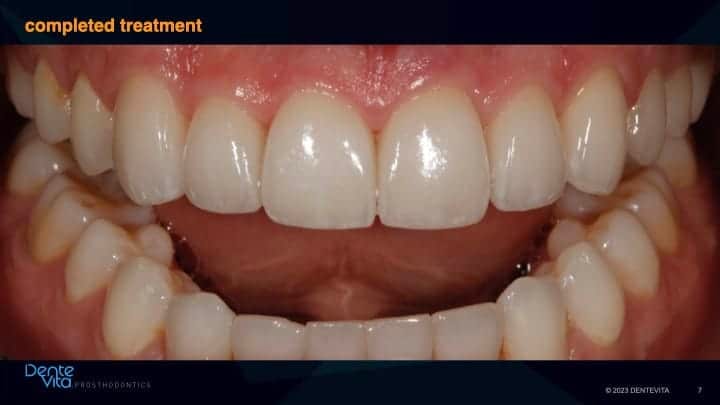

This case study addressed significant tooth erosion from gastric reflux. Lost vertical space from vertical tooth drift was reversed with orthodontic treatment (intrusion and alignment therapy).

After completion of successful orthodontic therapy, missing tooth structure was rehabilitated/restored with conservative 360 degree and three-quarter porcelain veneer therapy, along with posterior occlusal partial coverage onlay restorations.